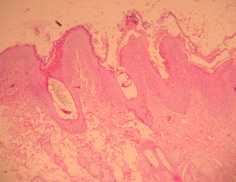

Les biopsies cutanées effectuées à l’aide d’un biopsy-punch au niveau des lésions des babines et de l’ars, (photos 5,6 et 7) montrent une dermatite superficielle périvasculaire hyperplasique avec

• hyperkératose ortho et parakératosique superficielle et infundibulaire (Photo 5)

cas-de-dermatose-amelioree-par-le-zinc-chez-une-jeune-chienne5Photo 5